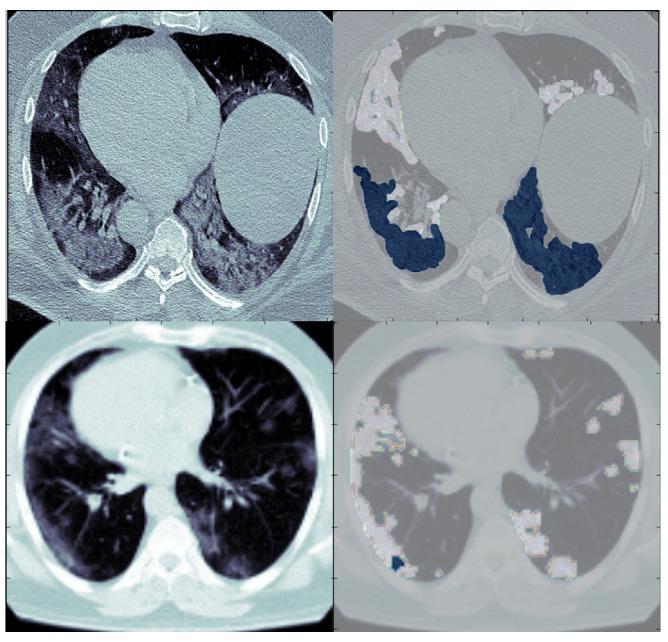

The disaster of the COVID-19 pandemic has claimed numerous lives and wreaked havoc on the entire world due to its transmissible nature. One of the complications of COVID-19 is pneumonia. Different radiography methods, particularly computed tomography (CT), have shown outstanding performance in effectively diagnosing pneumonia. In this paper, we propose a spatial attention and attention gate UNet model (SAA-UNet) inspired by spatial attention UNet (SA-UNet) and attention UNet (Att-UNet) to deal with the problem of infection segmentation in the lungs. The proposed method was applied to the MedSeg, Radiopaedia 9P, combination of MedSeg and Radiopaedia 9P, and Zenodo 20P datasets. The proposed method showed good infection segmentation results (two classes: infection and background) with an average Dice similarity coefficient of 0.85, 0.94, 0.91, and 0.93 and a mean intersection over union (IOU) of 0.78, 0.90, 0.86, and 0.87, respectively, on the four datasets mentioned above. Moreover, it also performed well in multi-class segmentation with average Dice similarity coefficients of 0.693, 0.89, 0.87, and 0.93 and IOU scores of 0.68, 0.87, 0.78, and 0.89 on the four datasets, respectively. Classification accuracies of more than 97% were achieved for all four datasets. The F1-scores for the MedSeg, Radiopaedia P9, combination of MedSeg and Radiopaedia P9, and Zenodo 20P datasets were 0.865, 0.943, 0.917, and 0.926, respectively, for the binary classification. For multi-class classification, accuracies of more than 96% were achieved on all four datasets. The experimental results showed that the framework proposed can effectively and efficiently segment COVID-19 infection on CT images with different contrast and utilize this to aid in diagnosing and treating pneumonia caused by COVID-19.

由于其传染性,新冠疫情这场灾难已夺去无数生命并给全世界造成了严重破坏。新冠病毒肺炎是新冠疫情的并发症之一。不同的影像学方法,尤其是计算机断层扫描(CT),在有效诊断肺炎方面表现出色。在本文中,我们受空间注意力UNet(SA - UNet)和注意力UNet(Att - UNet)启发,提出了一种空间注意力与注意力门控UNet模型(SAA - UNet),以解决肺部感染分割问题。所提出的方法应用于MedSeg、Radiopaedia 9P、MedSeg与Radiopaedia 9P的组合以及Zenodo 20P数据集。在上述四个数据集上,该方法显示出良好的感染分割结果(两类:感染和背景),平均Dice相似系数分别为0.85、0.94、0.91和0.93,平均交并比(IOU)分别为0.78、0.90、0.86和0.87。此外,它在多类分割中也表现良好,在四个数据集上的平均Dice相似系数分别为0.693、0.89、0.87和0.93,IOU分数分别为0.68、0.87、0.78和0.89。所有四个数据集的分类准确率均超过97%。对于二元分类,MedSeg、Radiopaedia P9、MedSeg与Radiopaedia P9的组合以及Zenodo 20P数据集的F1分数分别为0.865、0.943、0.917和0.926。对于多类分类,所有四个数据集的准确率均超过96%。实验结果表明,所提出的框架能够有效且高效地分割不同对比度CT图像上新冠病毒感染情况,并利用这一点辅助诊断和治疗新冠病毒引起的肺炎。